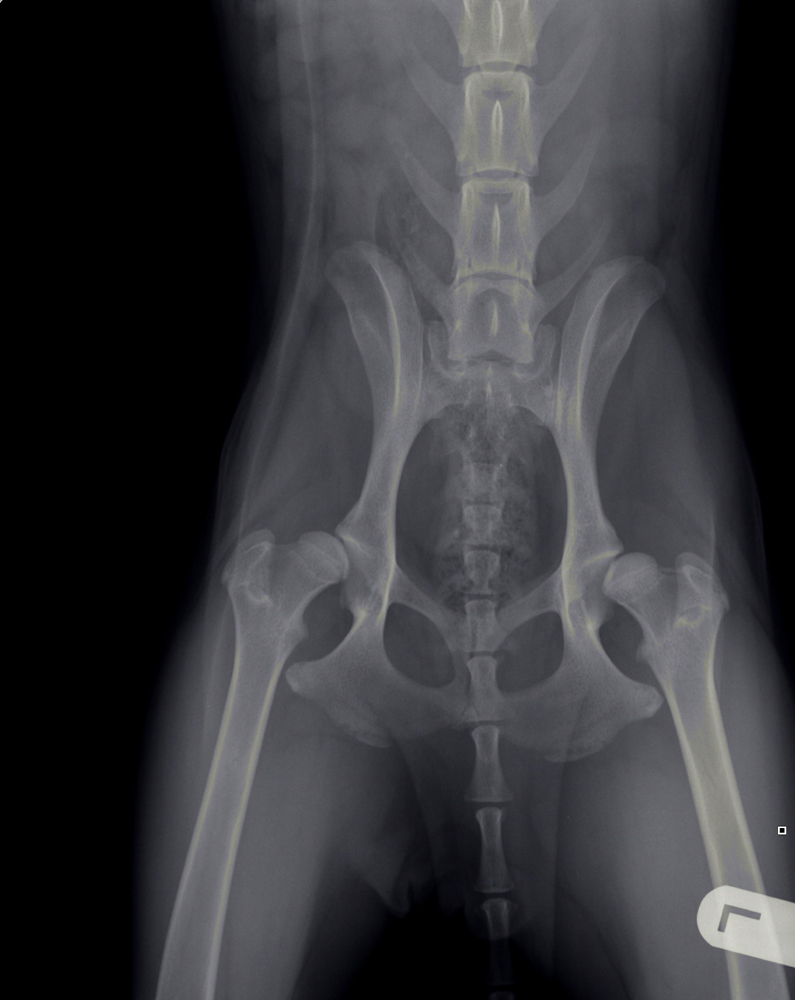

Heupdysplasie (HD)

Onder heupdysplasie wordt het volgende verstaan: een te ondiepe heupkom, waardoor de heupkop te veel ruimte heeft om te bewegen. Er is niet één enkele oorzaak voor te geven; meestal is het een combinatie van snelle groei, inspanning, voeding, leefomstandigheden en erfelijke factoren. Bij erfelijke factoren bestaat een aangeboren dysbalans tussen de spieren van het heupgewricht en de groei van bot, waardoor de heupkop niet goed in de kom wordt getrokken. Wat volgt is een abnormale ontwikkeling van het heupgewricht, wat kan leiden tot instabiliteit en daardoor irritatie van het gewrichtskapsel en het kraakbeen op de heupkop met artrose (=slijtage) als eindresultaat.

Artrose aan de heupen uit zich in het algemeen in bothaakjes aan de heupkop, verbreding van de hals van de heupkop (= de aansluiting van de heupkop met de rest van het dijbeen), onregelmatigheden in het bot van de heupkom en luxatie van de heupkop ten opzichte van de heupkom (heup geheel of gedeeltelijk uit de kom).

Met behulp van röntgenfoto’s kan de diagnose worden gesteld.